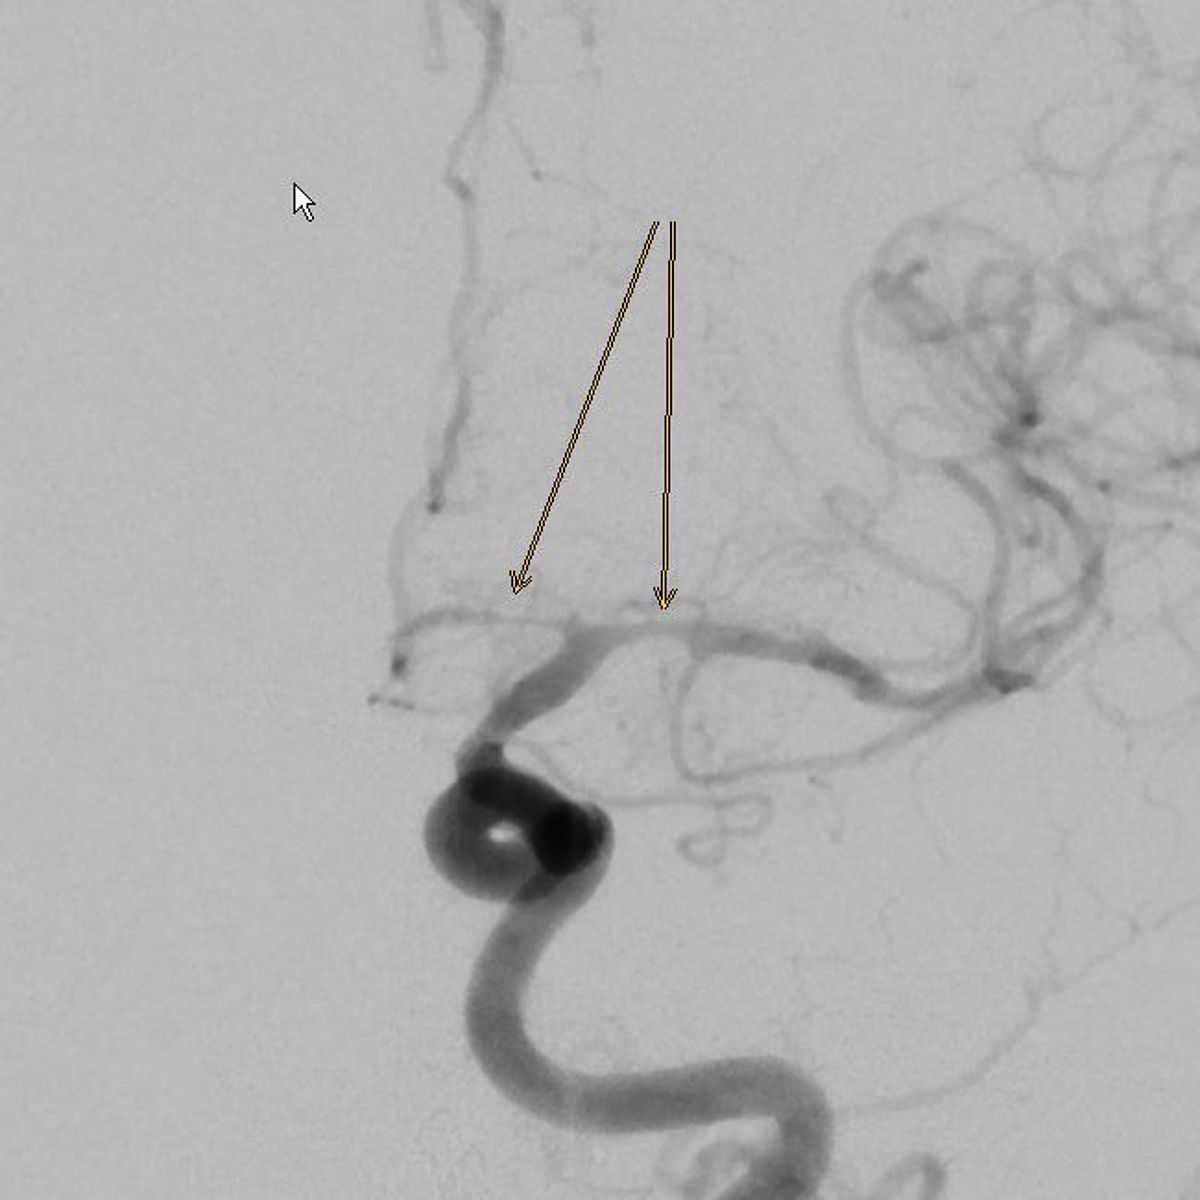

Die Hauptgefahr geht von einem Riss eines solchen Aneurysmas aus, was zu einer lebensgefährlichen Blutung in die Gehirnhäute oder das Gehirn führen kann (Subarachnoidealblutung).

In Augsburg werden im Jahr etwa 80 solcher akuter Subarachnoidealblutungen behandelt. Dabei ist neben der Behandlung der Blutungsfolgen vor allem die Ausschaltung des ursächlichen Aneurysmas dringlich, was meist interventionell durch die Neuroradiologie erfolgt.